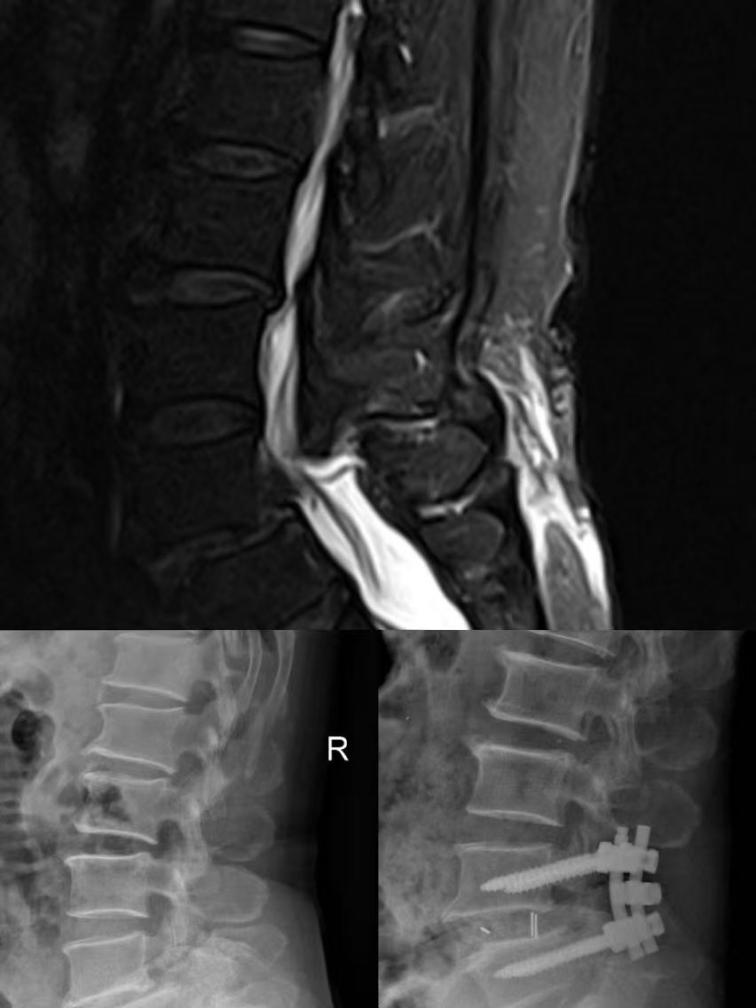

腰椎间盘突出症

在我国腰椎间盘突出及腰椎管狭窄症逐渐年轻化,亦可成为不可忽视的疾患。我科开展了一系列针对于每个病患的个体化治疗,针对于非手术治疗先天无法缓解的患者开展了脊柱内窥镜椎间盘切除手术(PELD)切口小,出血少,正常组织破坏小,使神经根获得有效减压。腰椎管狭窄症是由椎管发生的骨性和(或)纤维性狭窄引起的脊髓、马尾及脊神经根的压迫而出现的相应神经根功能障碍,通过有效检查详细为每一位患者针对性治疗,以及针对于保守治疗无效所开展常规腰椎管减压术、椎管成形术及腰椎管减压内固定术。

骨质疏松并发椎体骨折

高龄患者骨质疏松所致椎体压缩性骨折(OVCF)最新诊疗前沿。

高龄患者因骨质疏松在不经意间的胸腰背部活动即可致椎体骨折,通常人们会以扭伤忽视,认为休息后就可缓解,但往往收效甚微,老年患者常因持续疼痛而无法忍受。经皮穿刺椎体成形术(PVP或PKP)在治疗骨质疏松椎体骨折因它的显著疗效作为骨质疏松椎体压缩性骨折作为首选方案。切口长度仅6cm,手术创伤小,术后患者患部疼痛即可得到有效缓解,术后第二天即可鼓励患者穿戴腰围下床进行行走功能锻炼。经皮椎体成形术增强了椎体的稳定和强度,消除了骨折微功,防止椎体塌陷、骨不连,有效避免患者长期忍受疼痛以及后期脊柱畸形。

脊柱骨折(微创)

脊柱骨折是我科常见创伤。随着耕种、建筑业、交通、运动等项目的逐渐发展,其发生率有明显增高的趋势,并给家庭和社会带来沉重的负担。我科已走在脊柱创伤诊疗前沿,针对于不同程度、年龄的患者选择合理有效的治疗方案。经皮椎弓根螺钉固定技术是脊柱疾病治疗的革命性创新,为临床微创技术的发展提供了良好的助力,椎弓根螺钉内固定在脊柱三柱固定生物力学具有优越性,而经皮椎弓根螺钉固定技术对比开放性椎弓根内固定可以使手术微创化,切口小,对椎旁肌肉剥离少,手术出血量少,降低了传统手术入路对软组织广泛剥离和过度牵拉所造成的损伤,有效减少手术并发症的发生,患者术后康复更快。